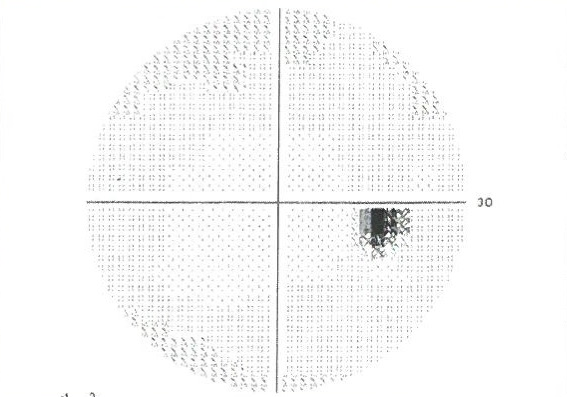

03.視野検査

緑内障の診断に視野検査はとても大切な検査です。緑内障の進行具合によって間隔は異なりますが、定期的に行う必要があります。当院では基本的にはハンフリー視野計で計測し、自動解析装置(ビーライン)で進行具合のチエックを行います。ハンフリー視野計で検査ができない場合や症状によっては、ゴールドマン視野計を用いて検査します。